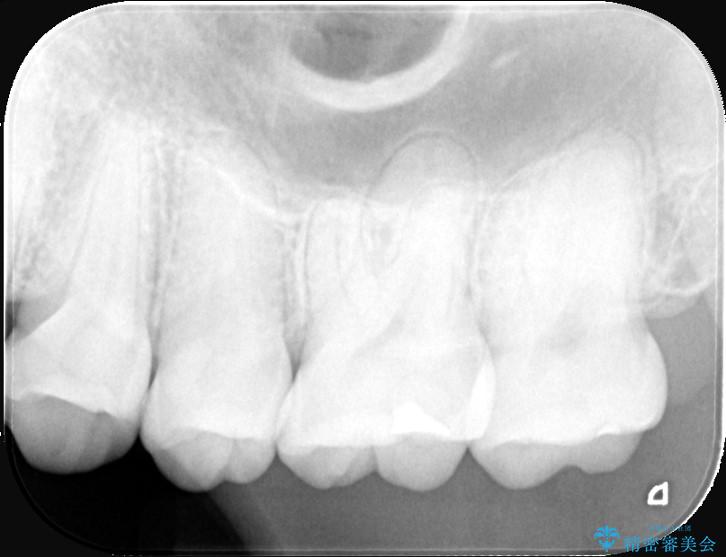

今回の治療では、虫歯の大きさや深さに応じて、異なるセラミック修復法を適用しました。

比較的軽度な虫歯には、セラミックインレー(詰め物)で対応し、健全な歯質を最大限に残しました。

進行した虫歯や歯の強度が低下している歯には、セラミッククラウン(被せ物)を選択し、歯全体を保護することで破折を防ぎました。